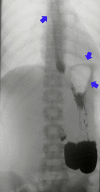

A 17-year-old girl was referred to our hospital with an inability to belch, while experiencing chest gurgling noises, and severe abdominal bloating. She reported having these symptoms all her life. A timed barium esophagogram revealed a moderate amount of bubbles in the esophagus and gastric fundus, which significantly increased after the examination. High resolution manometry revealed that the basal upper esophageal sphincter pressure increased with a rise in the cervical esophageal pressure. A pathological inability to belch is rare; at present, no specific name exists to describe the disorder. Further research is needed in this unexplored field.